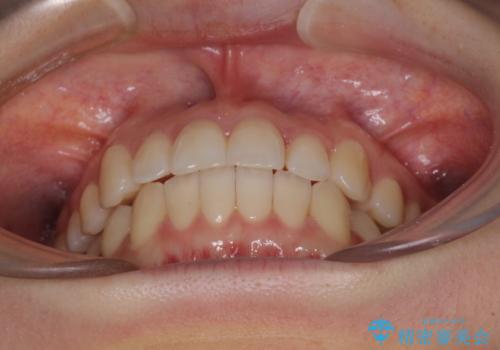

前歯のクロスバイト インビザラインによる矯正治療

- 前歯のクロスバイトを気にして来院された患者様です。

短期間での治療を希望され、ワイヤー装置とインビザラインとで悩んでいましたが、自己管理を徹底すると言うことでインビザラインによる矯正治療を行うこととしました。

しっかりとインビザラインの装着時間を守っていただいたので、1年弱で矯正治療を終えることができました。